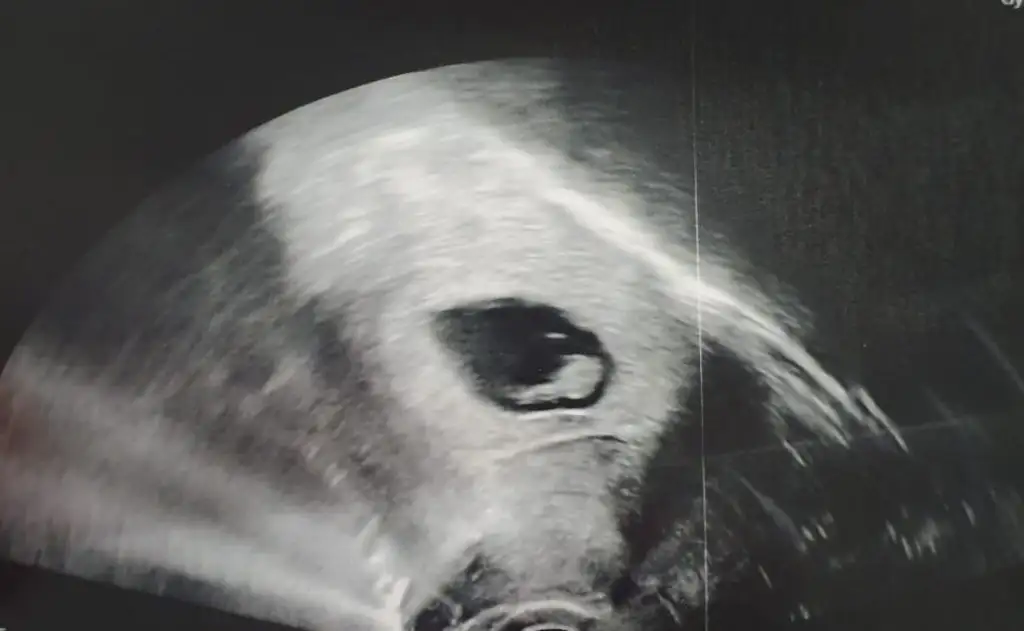

kuzum baksana uzandığı yer dümdüz sağda da duruyor bu bence kızSelam kızlar. Arkadaşımın USG fotosu cinsiyet tahmini alabilir miyiz. Karından bakıldı bu arada

Evet karından yazmayı unutmuşum. Yorumunuz için çok teşekkür ederim. Cinsiyeti öğrendiğimde yazacağım.kuzum karından bakılmıştır diye tahmin ediyorum. Tosun paşa gibi duruyor.